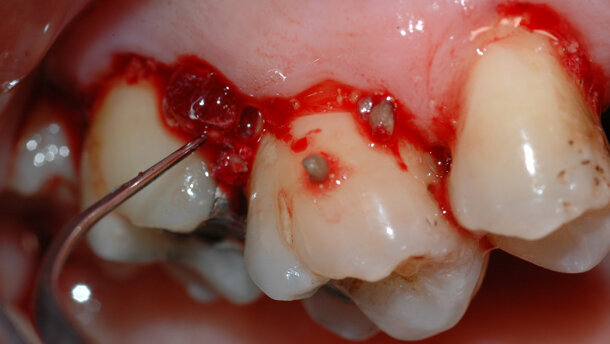

- Indipendentemente dal protocollo adottato, è essenziale che la strumentazione parodontale non chirurgica cerchi di rimuovere tutto ciò che è estraneo al dente (Biofilm microbico, tartaro, discromie) e al contempo rispetti la sostanza biologica.

In altre parole, l’obiettivo principale è rimuovere il fattore eziologico, che provoca l’infiammazione, nel modo più efficace e consono alla manualità e alle conoscenze tecniche dell’operatore, pur rispettando esigenze, anche di logica organizzativa, espresse dal paziente. Non si tratta cioè di uno schema rigido cui attenersi, i protocolli possono e devono essere personalizzati e conseguentemente modificati. Se possibile si consiglia di cominciare e completare la fase non chirurgica iniziale (i tre appuntamenti di un’ora ciascuno) entro la prima settimana1, proprio perché una volta individuata la patologia e la sua causa eziologica, rimuovere efficacemente quest’ultima consente di accelerare i processi di guarigione, migliorando probabilmente l’esito del trattamento. I progressi nel campo delle conoscenze di microbiologia parodontale, associati alle migliorie tecnologiche, possono aiutarci sia a capire l’esatta natura delle infezioni parodontali, sia a eseguire un trattamento nel modo più efficace e rapido possibile2. In occasione di ogni appuntamento viene sottoposta a strumentazione parodontale non chirurgica l’intera cavità orale. Ovviamente, la prima seduta sarà dedicata alla strumentazione sopra-gengivale, utilizzando prevalentemente strumenti a ultrasuoni in caso di abbondanti depositi; l’utilizzo del laser deve precedere la strumentazione sotto-gengivale, se si ravvedono indicazioni al suo utilizzo.

È molto importante strumentare ogni volta tutta la cavità orale, al meglio delle nostre possibilità; com’è naturale, non sarà verosimile rimuovere in maniera completa il tartaro sotto-gengivale, soprattutto in occasione del primo appuntamento, viceversa è possibile ridurre i depositi in maniera significativa. È comunque inevitabile lasciare depositi residui, ma questi dovranno essere distribuiti un po’ “a macchia di leopardo”. Importante evitare l’errore di strumentare soltanto i primi millimetri sotto la gengiva, facilmente raggiungibili; ancora peggio, illudersi di strumentare i soli depositi sopra gengivali. Questo provocherebbe il rischio di un episodio acuto, successivo alla seduta di strumentazione parodontale non chirurgica, definito come “effetto polsino”3.